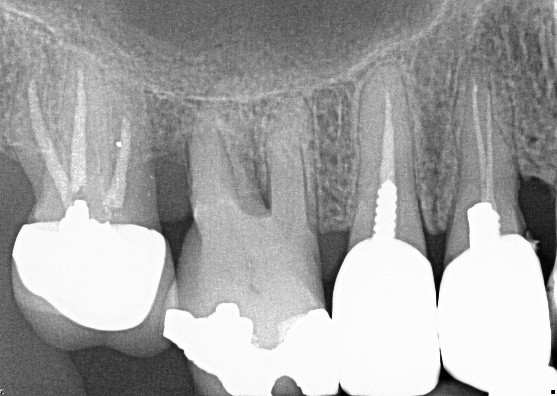

The radiograph shows evidence of

The radiograph shows evidence of calculus on

Which of the following is true regarding dental implant at site 2.6?

Which of the following is true regarding dental implant at site 3.6?

There is radiographic evidence of

Regarding tooth 4.6, there is evidence of

Regarding dental implant at site 3.6, there is evidence of

Which of the following is/are seen in the radiograph?

Which of the following is/are seen in the radiograph for tooth 3.6?

Which of the following is/are seen in the radiograph for tooth 3.7?

Which of the following is/are seen in the upper right quadrant of this panoramic radiograph?

Tooth 1.6 shows evidence of

The radiograph shows evidence of periodontal bone loss on